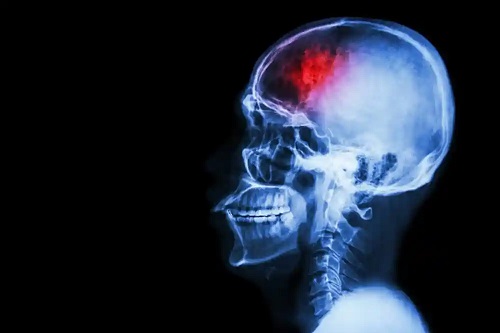

Carotidele sunt o pereche de artere mari care se află pe ambele părți ale gâtului. Ele sunt responsabile de furnizarea de sânge de la aortă către față, creier și diferite structuri craniene. La nivelul creierului, ele hrănesc regiuni legate de funcțiile motorii și senzoriale, precum și de vorbire, gândire și personalitate.

Blocajul vascular reduce fluxul de sânge către creier și crește riscul de accident vascular cerebral ischemic. Acesta din urma apare în cazul unei ocluzii sau întreruperi totale a irigării arterelor carotide. Oprirea fluxului sanguin către creier lasă neuronii fără oxigen și aceștia mor.

Stenoza carotidiană aterosclerotică sau ocluzia cauzează aproximativ 30% din cazurile de ischemie cerebrovasculară, potrivit cercetărilor. Aceasta este o complicație cu risc ridicat, cu o rată ridicată a mortalității dacă nu se administrează un tratament în timp util.